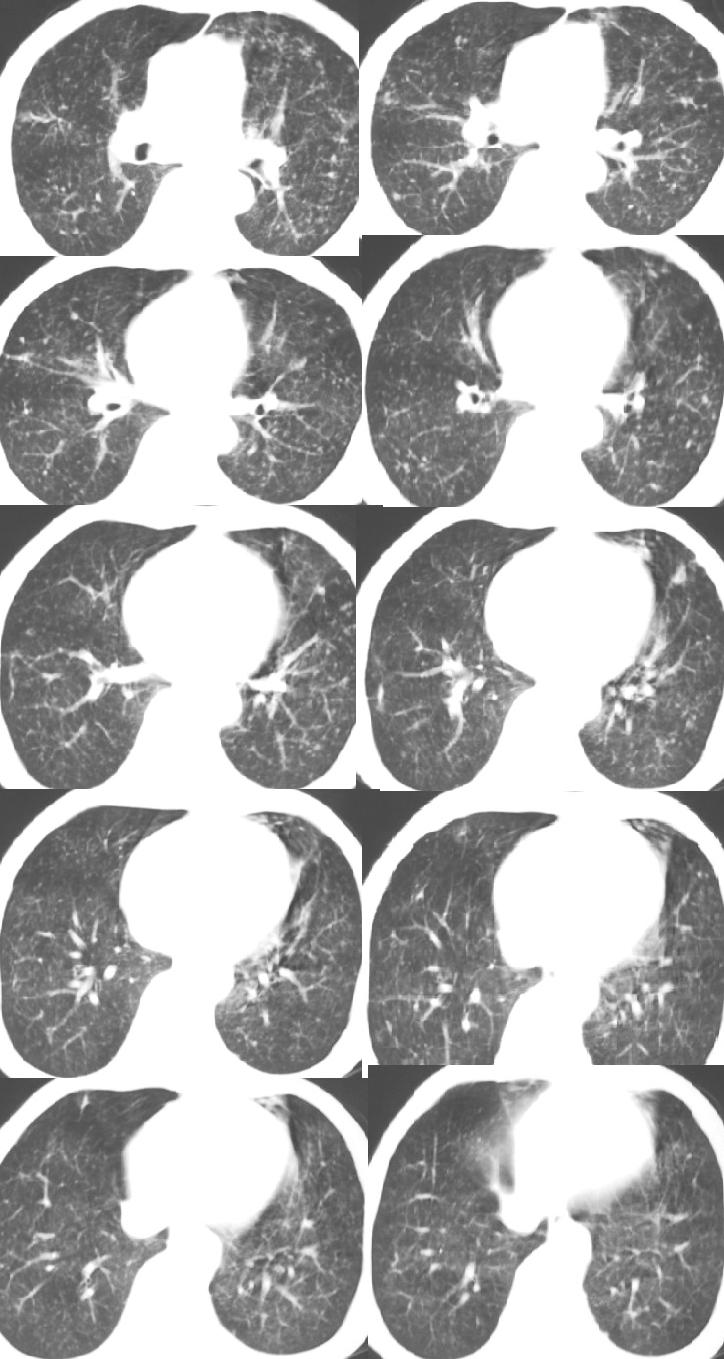

以下是引用医影拾贝在2008-6-3 18:48:00的发言:[br]双上肺弥漫性小结节影,纵隔窗内钙化淋巴结影,考虑血播性tb可能性较大,不除外肺ca可能

以下是引用jinguoji在2008-6-3 20:20:00的发言:[br]双上肺弥漫性小结节影,纵隔窗内钙化淋巴结影,考虑血播性tb可能性较大,不除外肺ca可能。腰椎考虑退变。

以下是引用卜一在2008-6-3 19:33:00的发言:[br]双肺结节,以双上肺分布为多,期间搀杂片状致密影及索条致密影。考虑:继发性肺结核伴血型播散可能性大。不除外肺泡ca的可能!另:椎体退变!

以下是引用panyishengct在2008-6-3 21:09:00的发言:[br]双上肺弥漫性小结节影,纵隔窗内钙化淋巴结影,考虑矽肺或/和tb可能性较大,不除外肺ca可能。腰椎考虑退变。 [br][br]